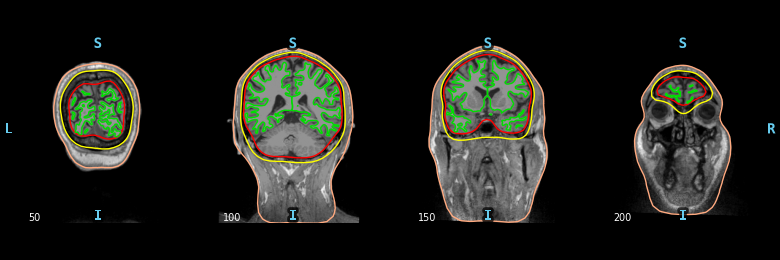

Compute and visualize BEM surfaces#

The BEM surfaces are the triangulations of the interfaces between different tissues needed for forward computation. These surfaces are for example the inner skull surface, the outer skull surface and the outer skin surface, a.k.a. scalp surface.

For EEG we use 3 layers (inner skull, outer skull, and skin) while for MEG 1 layer (inner skull) is enough.

Let’s look at these surfaces. The function mne.viz.plot_bem()

assumes that you have the bem folder of your subject’s FreeSurfer

reconstruction, containing the necessary surface files. Here we use a smaller

than default subset of slices for speed.

plot_bem_kwargs = dict(

subject=subject,

subjects_dir=subjects_dir,

brain_surfaces="white",

orientation="coronal",

slices=[50, 100, 150, 200],

)

mne.viz.plot_bem(**plot_bem_kwargs)

Using surface: /home/circleci/mne_data/MNE-sample-data/subjects/sample/bem/inner_skull.surf

Using surface: /home/circleci/mne_data/MNE-sample-data/subjects/sample/bem/outer_skull.surf

Using surface: /home/circleci/mne_data/MNE-sample-data/subjects/sample/bem/outer_skin.surf